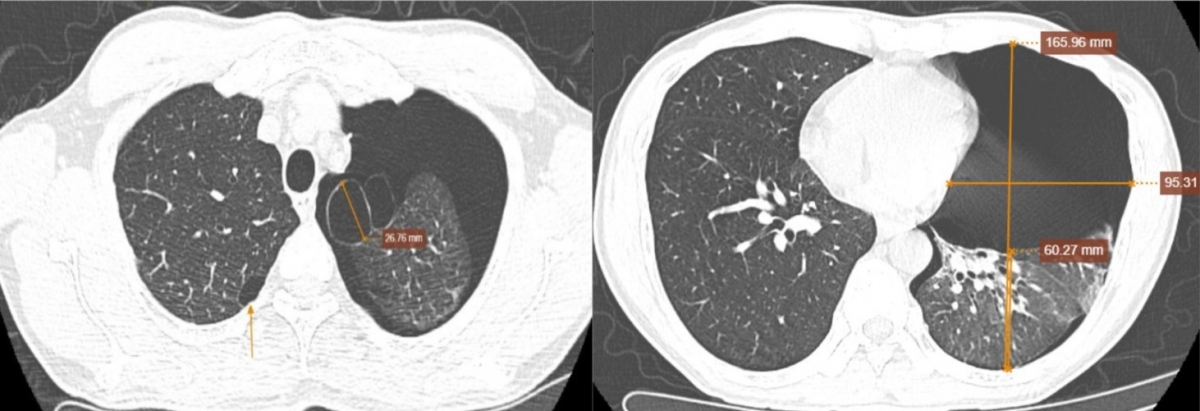

Kết quả chụp cắt lớp vi tính phổi liều thấp ghi nhận: hình ảnh tràn khí khoang màng phổi trái gây xẹp thụ động nhu mô phổi (khoảng 75%), nghĩ đến do vỡ kén khí; kén khí thùy trên phổi trái; giãn phế nang cạnh vách thùy trên hai phổi.

Kết quả siêu âm tim và màng phổi cho thấy: tim lệch phải do tràn khí màng phổi mức độ nhiều; mất dấu trượt màng phổi, mất đường lines B; kích thước các buồng tim bình thường; chức năng tâm thu thất trái bình thường; không tăng áp lực động mạch phổi.